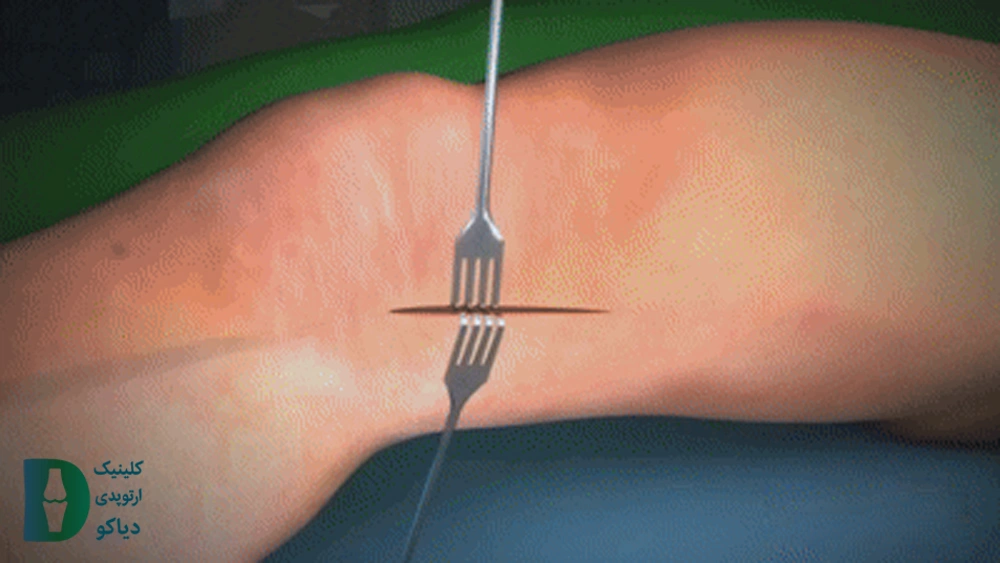

در جراحی هدایت رشد یک پلاک بهاندازه گیره کاغذ روی بخشی از صفحه رشد استخوان توسط پیچ متصل میگردد. کار این پلاک جلوگیری از رشد برخی قسمتهای استخوان است. بدین صورت که با رشد بخشهای خاصی از استخوان فرم زانو اصلاح میشود. این جراحی 20 الی 40 دقیقه طول میکشد.

در این جراحی ابتدا برش پوست و کنار زدن عضلات زیر آن در قسمتی از پا که برای جراحی در نظر گرفته شده است انجام میشود و برای دقیق بودن جراحی از یک صفحه کوچک به عنوان الگو استفاده میشود. در مرحله بعد استخوان (ران یا ساق پا) به دو روش تحت برش قرار میگیرد که به تشخیص پزشک بستگی دارد.

در این جراحی، ابتدا پوست در ناحیهی موردنظر برش داده میشود و عضلات زیر آن بهطور موقت کنار زده میشوند تا استخوان نمایان شود. برای دستیابی به دقت بالا در اصلاح زاویه، از یک صفحهی فلزیکوچک بهعنوان راهنما استفاده میگردد.